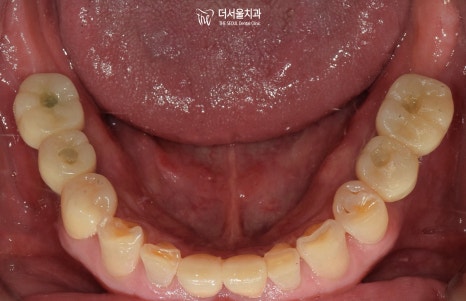

초진 구강 사진을 보면

곳곳에 이가 빠져서 빈 곳이 있고

남아있는 이들이 깨지고

벌어져있습니다.

대구치는 큰 음식을 잘게 부수고

어느정도 단단하고 질긴 것을 씹을 수 있으며

그 힘을 견딜 수 있는 크기와

형태, 구조로 이루어져 있습니다.

그런데 문정역치과 환자분의 경우,

면종류를 끊어먹는 정도의 기능을 하는

앞니가 어금니의 역할을 대신하게 되면서

그 힘을 견디지 못하고

이가 부러져버리고 벌어지는

문제가 생겨나게 된 것이죠.